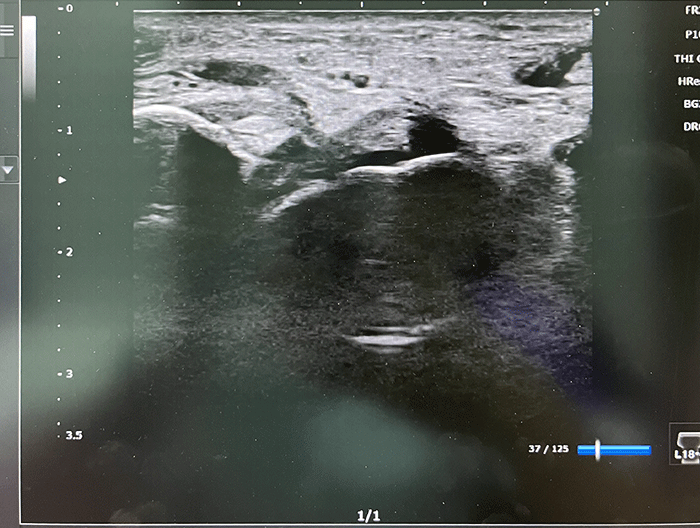

こちらは足首の捻挫のエコーです。下の画像が正常で上の画像が断裂した様子です。